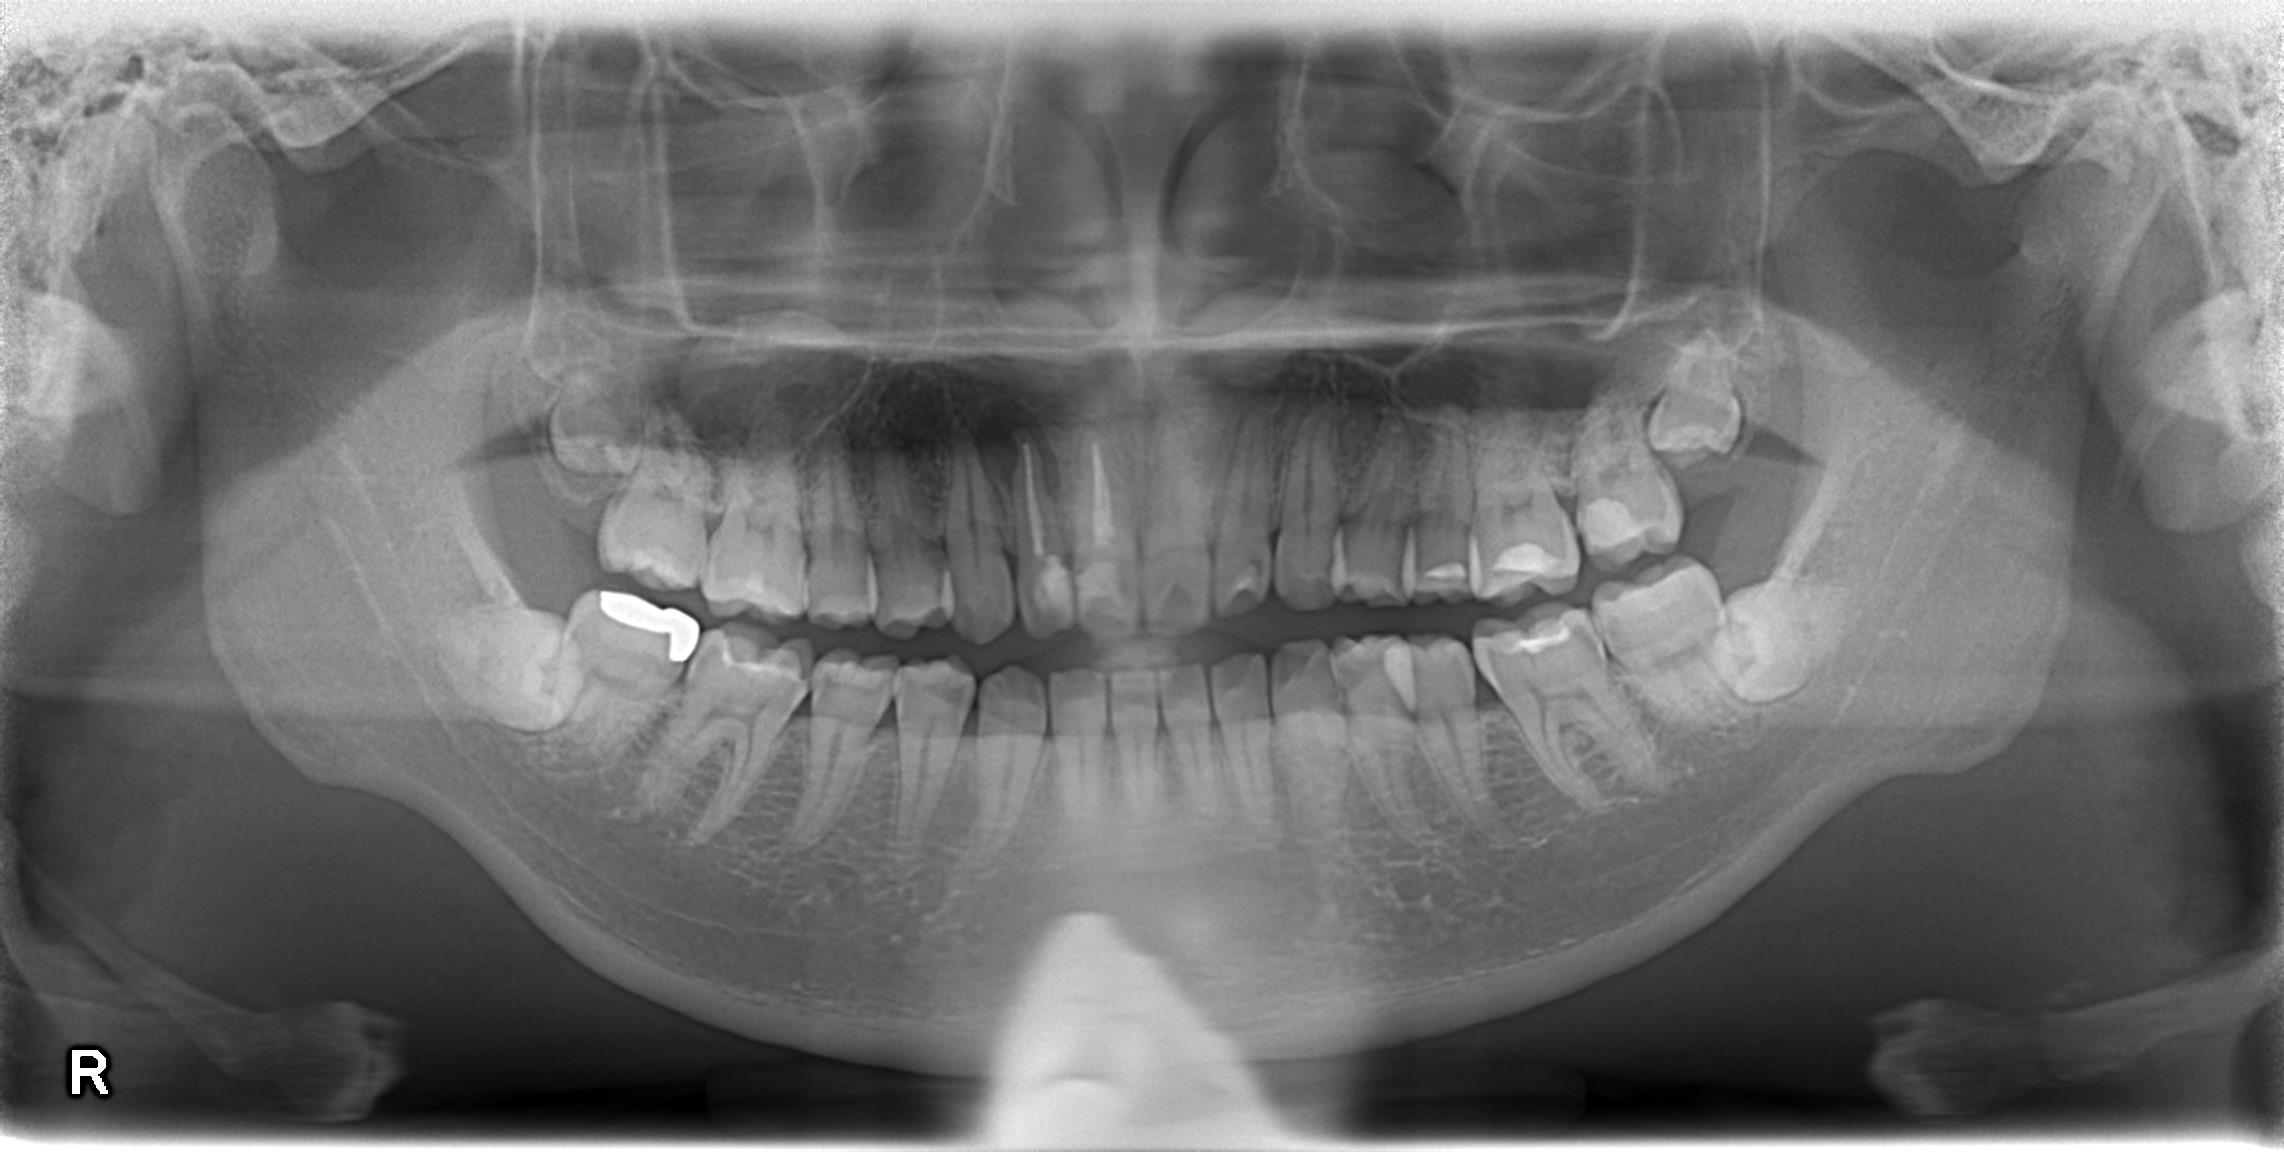

右上の前から2番目の歯に大きな病変ができています。

これは、慢性根尖性歯周炎と診断される状態です。

歯の周りを、通常は骨が取り囲んでいるのですが、その骨が炎症によりなくなってしまい、レントゲン上で黒く写るのです。

①先端まで材料がはいっていないこと

②根管の途中が、やや詰まりきっていないこと

が伺えます。